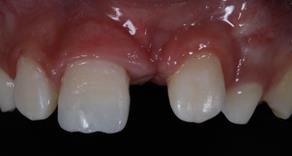

An 8-year-old male patient attended the Emergency Children's Dental Care at the Children's Specialties Clinic-Baby-Clinic of the State University of Londrina, for immediate treatment after a fracture in the right upper central incisor due to a fall during a school sports activity. On intraoral physical examination, a coronal fracture of the enamel and dentin was diagnosed without involvement of the pulp tissue (Figure 1). Response to the vertical and horizontal percussion test was not suggestive of endodontic and periodontal alterations, respectively, and impairment of the periodontal insertion was also ruled out through the mobility test in the buccal-palatal direction.On radiographic examination (Figure 2) confirmed the absence of periodontal and periapical involvement, as well as the absence of root fracture.